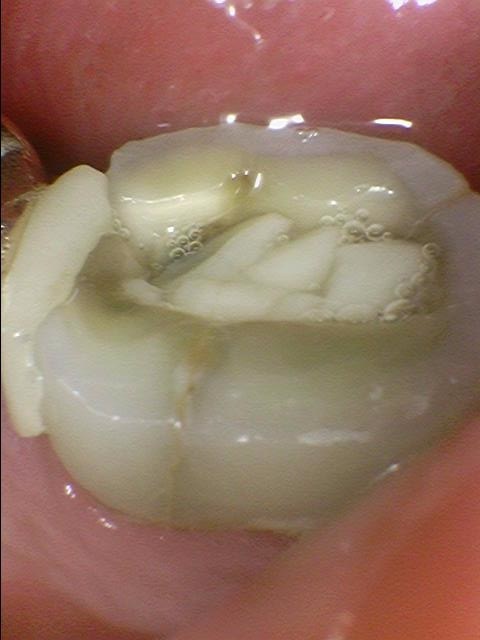

딱딱한 과자를 먹었는데 그 후로 누르거나 씹을 때 통증이 있다고 오신 환자분입니다.

치아에 금이 간 것이 보이고 핀셋으로 만져보면 벌어집니다.

세로로 금이 간 것이 3차원 ct에서 희미하게 보입니다.

아주 미세한 금은 ct에서 안보일수도 있습니다.

금이 깊은 것을 확인하고 발치 하였고

발치해보니 치아가 뿌리 일부까지 금이 가서

3덩어리로 나누진 상태였습니다.